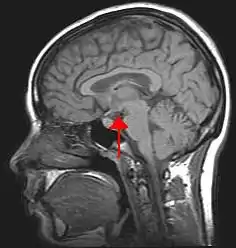

The central nervous system includes the brain and spinal cord. The brain and spinal cord are protected by bony structures, membranes, and fluid. The brain is held in the cranial cavity of the skull and it consists of the cerebrum, cerebellum, and the brain stem. The nerves involved are cranial nerves and spinal nerves.

The "Central Nervous System", comprised of the brain, brain stem, and spinal cord.